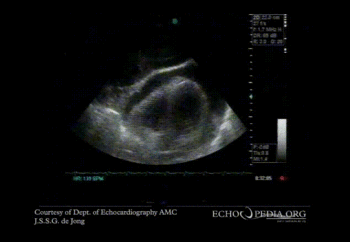

The apical 4 chamber echocardiogram shows severe pericardial effusion and a swinging heart.

An apical 4 chamber view of a swinging heart